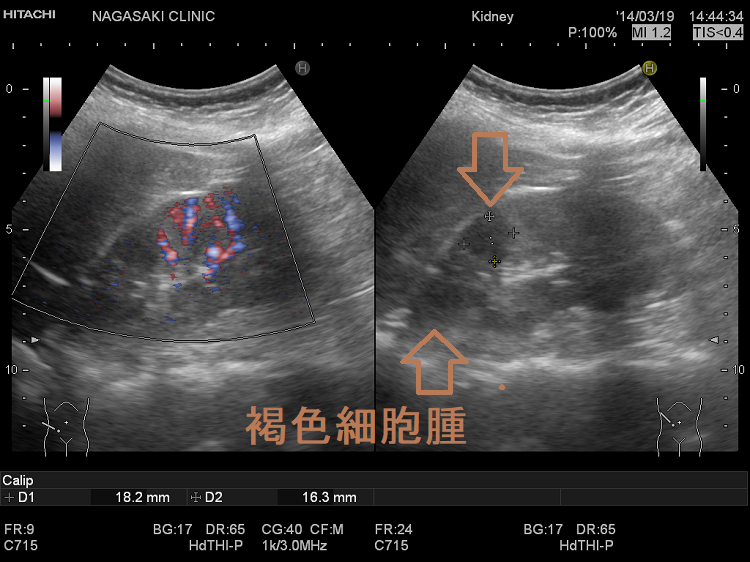

副腎腫瘍(褐色細胞腫) 超音波(エコー)画像

1. 褐色細胞腫の存在が既に判っており、腫瘍内出血がある場合、腹部超音波(エコー)、腹部単純CTで褐色細胞腫内の液面形成を確認